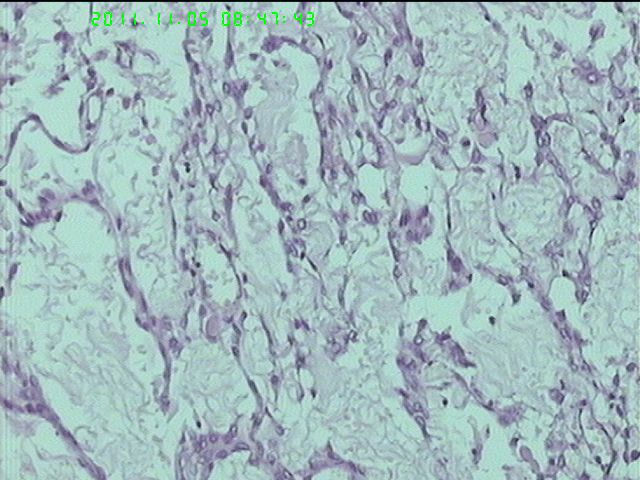

37岁女性患者,左卵巢肿块术中快速:恶性。术后左卵巢囊实性肿块14*9*5CM,灰黄色,部分乳头状,粘液样外观;子宫内膜厚1.5CM;网膜见多个小结节。图1--14左卵巢  15-19网膜  20--23宫腔

在图中有明确浸润吗?好像看不出来,但是网膜显示非侵袭性。宫腔图片没有显示浸润。请多上边缘处图像。

请临床查有无阑尾病变,排除阑尾肿瘤转移后,如果没有明确浸润,倾向粘液性*交界性肿瘤伴腹膜种植,肠型。

总之先排除阑尾来源,再看有无浸润,有浸润才打癌。